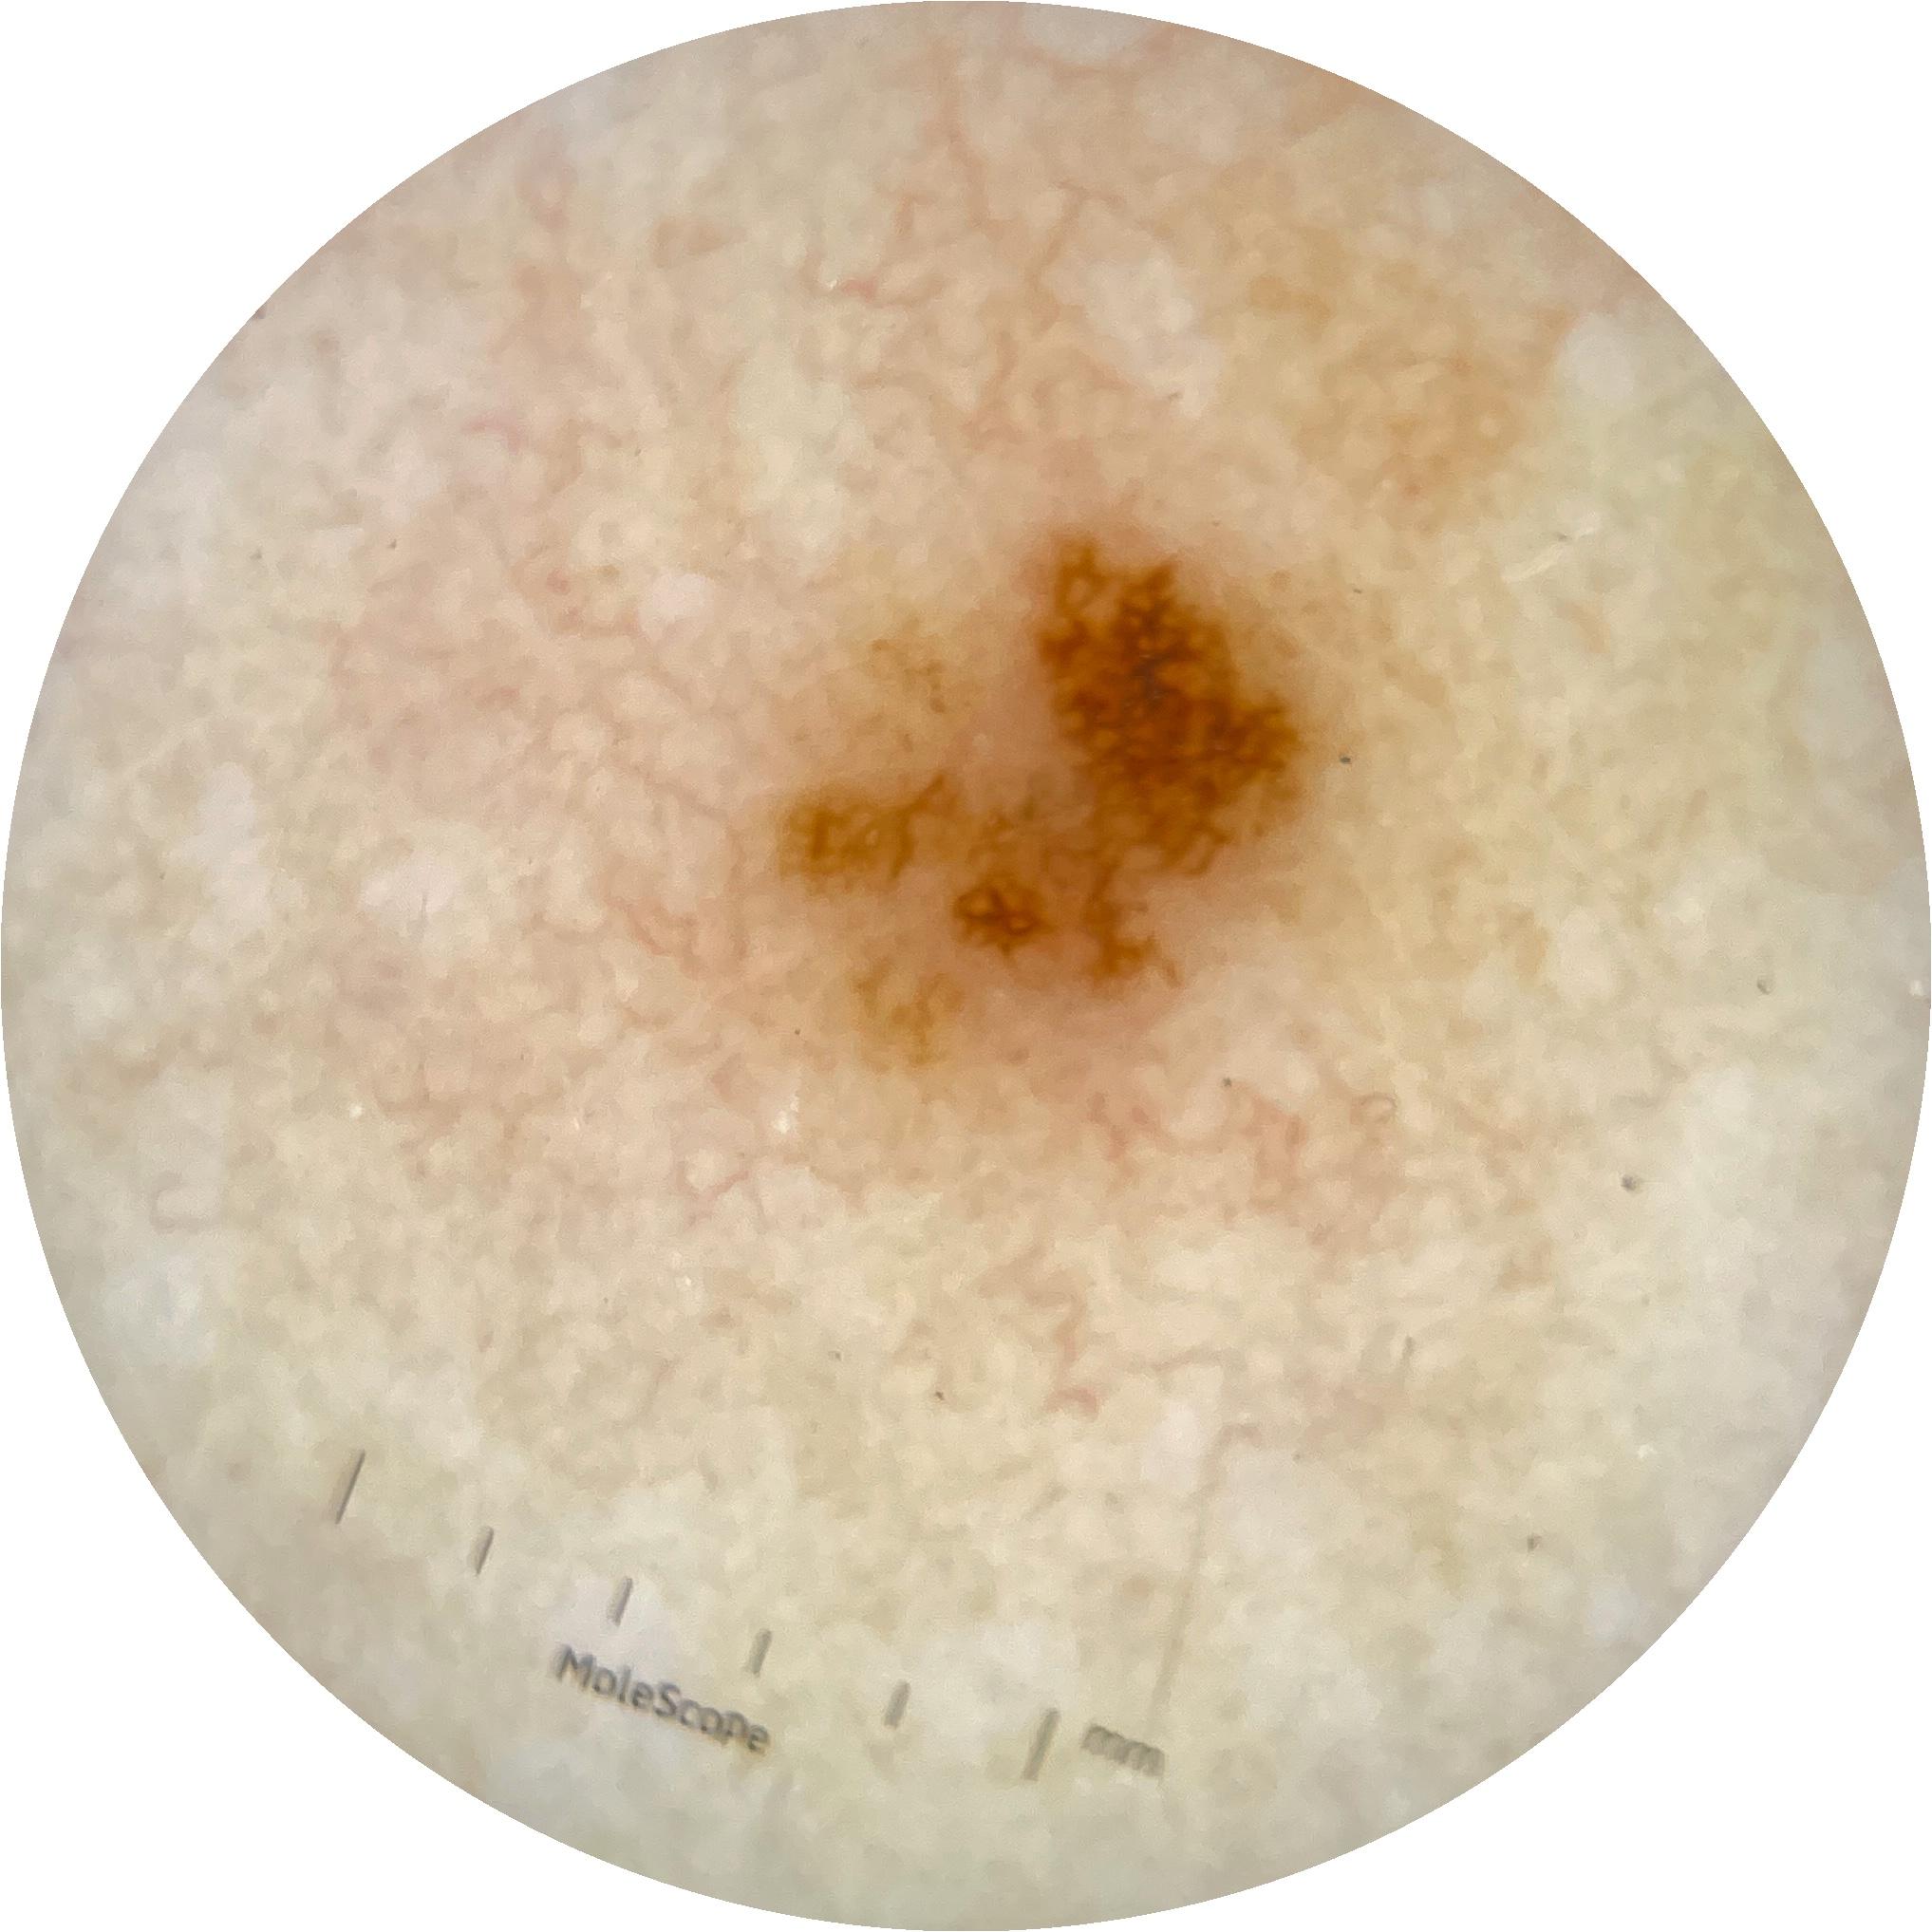

ISIC_6476310

2001 x 2001

acquisition_day 463

age_approx 40

anatom_site_1 Trunk

anatom_site_2 Anterior trunk

anatom_site_general anterior torso

diagnosis_1 Benign

diagnosis_confirm_type single image expert consensus

image_type dermoscopic